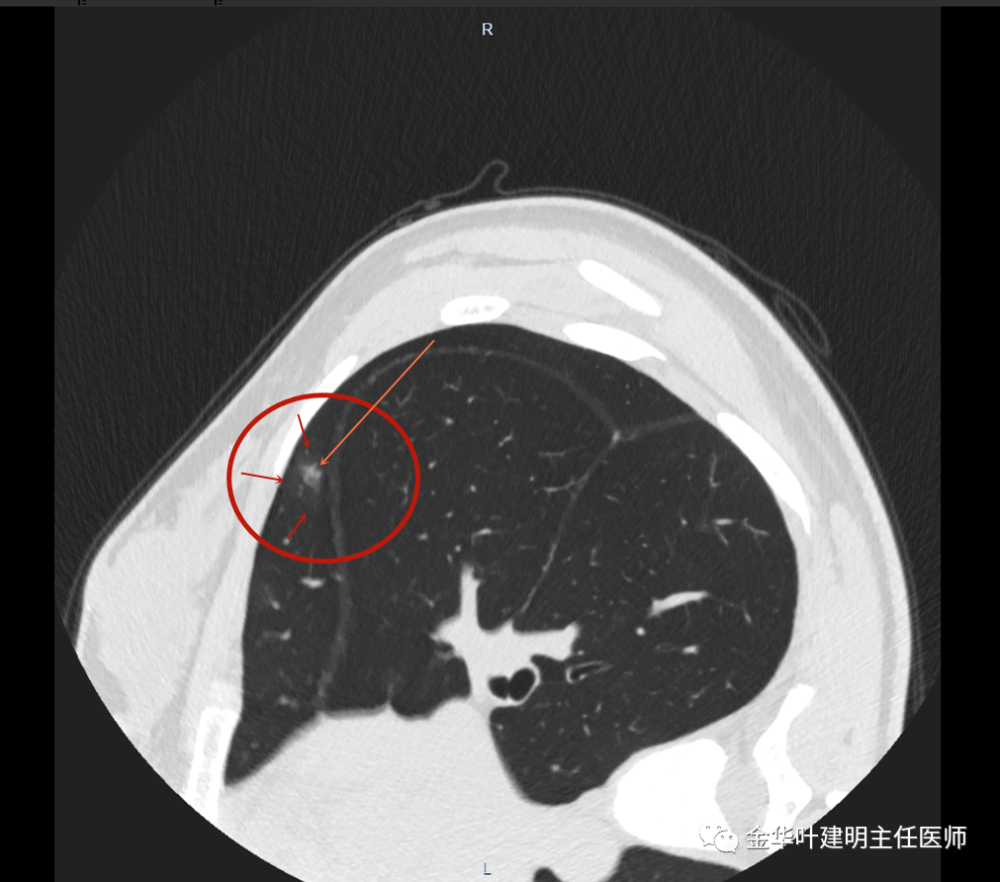

右肺玻璃结节

右肺玻璃结节,

肺磨玻璃结节可以随访多久

正确认识面对肺部磨玻璃结节

经验积累202139年轻的肺混合磨玻璃结节请复查一下

右肺上叶另见伴有小空泡的淡而微小磨玻璃结节,见蓝色圈起来的地方